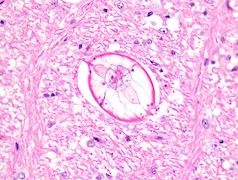

z toksycznym działaniem pasożytów: drżenia mięśniowe, zaburzenia psychiczne i neurologiczne oraz uszkodzenie wątroby. Pasożytem wywołującym chorobę jest przywra Opisthorchis felineus. Opistorchoza jest chorobą przewodów żółciowych i wątroby, ale przywra kocia Opisthorchis felineus może również występować w innych miejscach w organiźmie. Jest to plaski robak szerokości do 2mm i długości do 13mm. Przywra potrzebuje, do swojego rozwoju, żywicieli pośrednich. Pierwszym z nich są zazwyczaj ślimaki bythynia, drugim ryby słodkowodne. Ludzie zarażają się zjadając zarażone ryby niepoddane starannej obróbce termicznej (np sushi lub wędzone na zimno), owoce morza, kawior. Prawdopodobnie możliwe jest także zakażenie poprzez zjedzenie niedomytej zieleniny oraz surówek i sałatek zawierających pośrednie formy rozwojowe. Po zakażeniu przywra dostaje się do dróg żółciowych, gdzie osiąga dojrzałość. Przywra kocia uszkadza jelita, miąższ wątroby i przewody żółciowe. W przypadku występowania dużej liczby przywr możliwe jest zaczopowanie przewodów żółciowych. Opistorchoza sprzyja również infekcjom bakteryjnym oraz uczuleniom i stanom zapalnym.

Opistorchoza często przebiega bezobjawowo lub jest mylona z innymi objawami. Pojawiające się objawy mają z reguły niecharakterystyczny przebieg. W opistorchozie występuje gorączka, bóle brzucha, powiększenie wątroby i śledziony, wymioty, tworzenie się kamieni żółciowych, osłabiony apetyt, zaburzenia przewodu pokarmowego, kłucia podżebrowe i kolki wątroby oraz zapalenie dróg żółciowych. Przywry w przewodach żółciowych wywołują odpowiedź zapalną. Często też dochodzi do występowania zgagi oraz wyrzutów insulinowych.Przewlekła postać zakażenia przywrą kocią przebiega podobnie jak zarażenie przywrą chińską Clonorchis sinensis. Objawy kliniczne pojawiają się na skutek mechanicznego drażnienia przewodów żółciowych i toksycznego działania pasożytów. Obecność pasożytów w drogach żółciowych powoduje lokalne reakcje tkankowe, m.in. intensywny rozrost nabłonka i tkanki łącznej oraz zwłóknienia. Na obszarach częstego występowania opistorchozy u większości zarażonych osób nie pojawiają się objawy. Jeśli pojawiają się ostre objawy, dochodzi do tego najczęściej w wyniku pierwszego zarażenia pasożytem. Mogą wystąpić wtedy dreszcze, narastająca lub nagła gorączka do 40 stopni Celsjusza, bóle w nadbrzuszu, powiększenie wątroby i śledziony.

W obrazie histopatologicznym przewodów żółciowych stwierdza się silne infiltracje tkanki nabłonkowej leukocytami, powodujące zmiany zapalne i zwłóknienia. Przywry mogą występować w przewodach trzustkowych, co może powodować zapalenie trzustki.